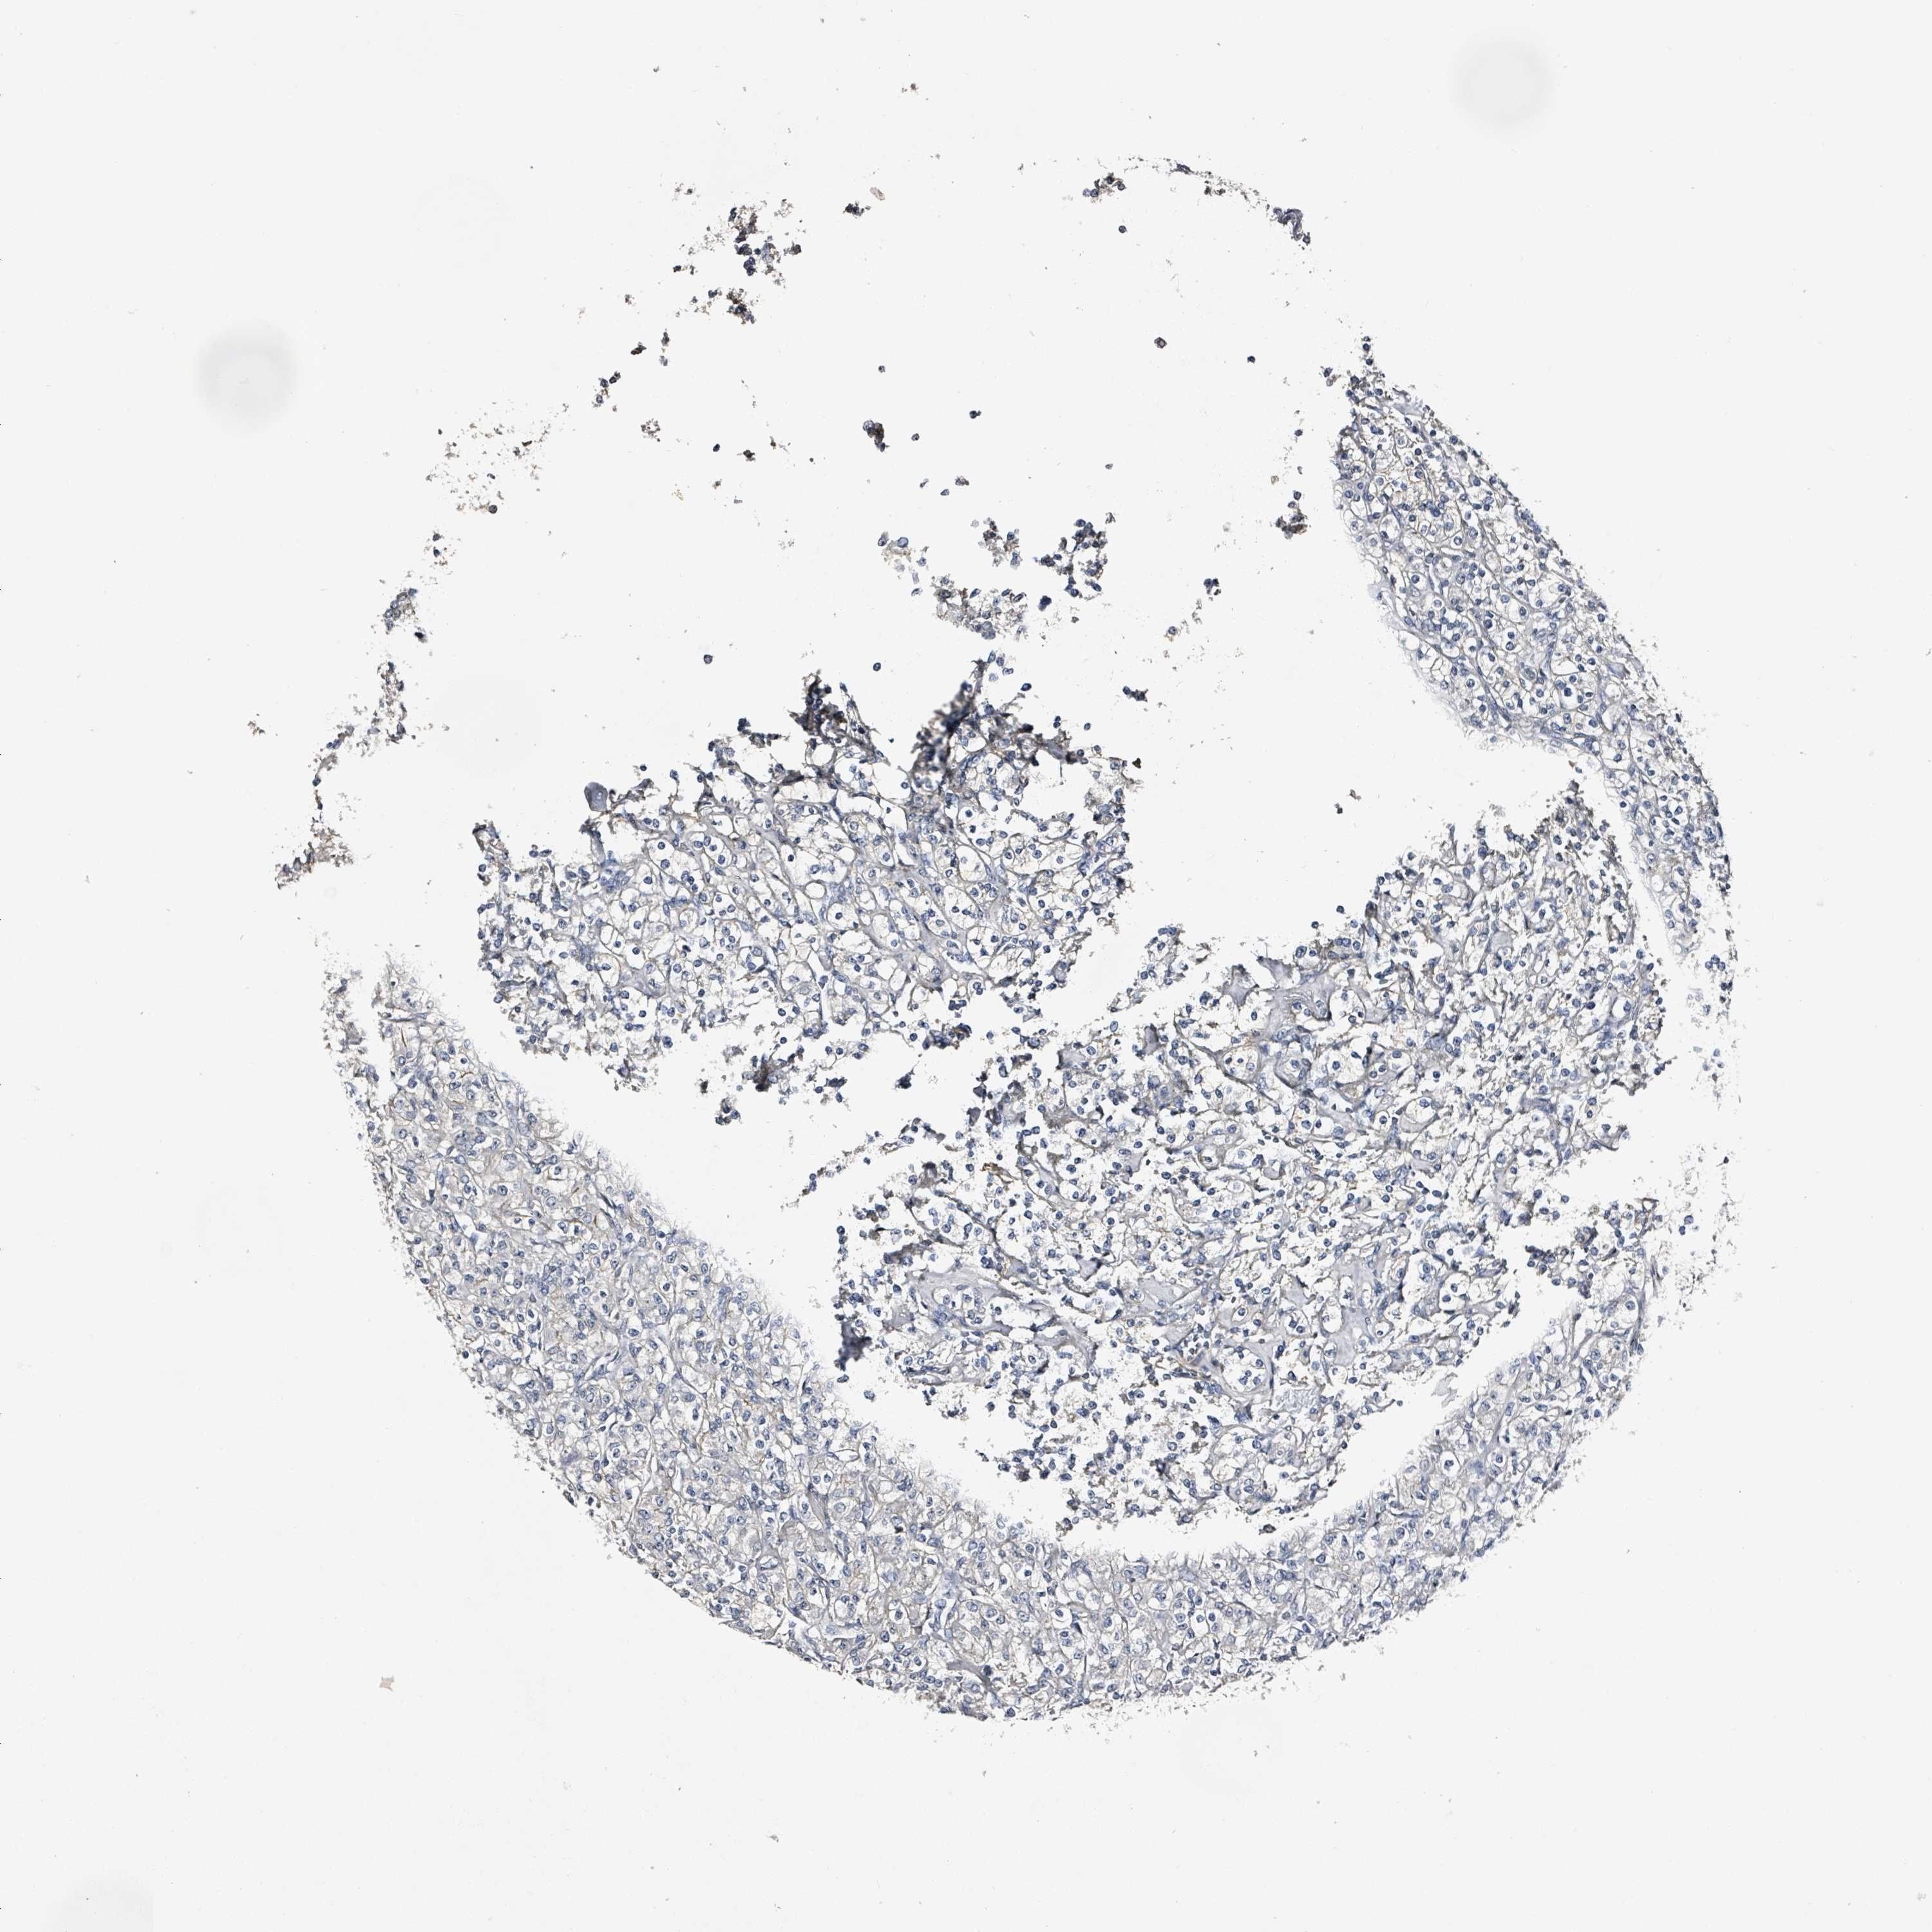

CANCER RENAL CANCER Show tissue menu

KICH TCGA KIRC TCGA KIRC VALIDATION KIRP TCGA PROTEIN RCC CPTAC PROTEIN EXPRESSION